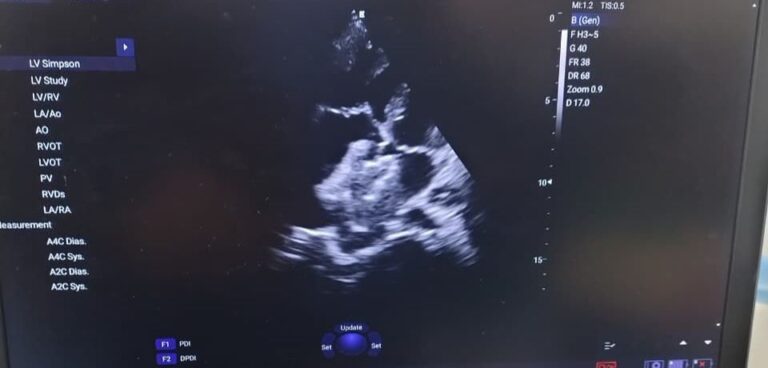

हेल्थ/सिटी डेस्क, Taj News | Updated: Wednesday, 21 Jan 2026 09:30 PM IST आगरा: ताजनगरी आगरा के ऐतिहासिक सरोजिनी नायडू मेडिकल कॉलेज (SNMC) ने चिकित्सा के क्षेत्र में एक और सुनहरा अध्याय जोड़ दिया है। कॉलेज के 170 साल के इतिहास में पहली बार कार्डियोलॉजी विभाग ने बिना ‘ओपन हार्ट सर्जरी’ (Open Heart Surgery) के … Continue reading Agra News: एसएन मेडिकल कॉलेज के डॉक्टरों का कमाल; बिना चीर-फाड़ के बंद किया दिल का छेद, 170 साल के इतिहास में पहली बार मिली यह कामयाबी